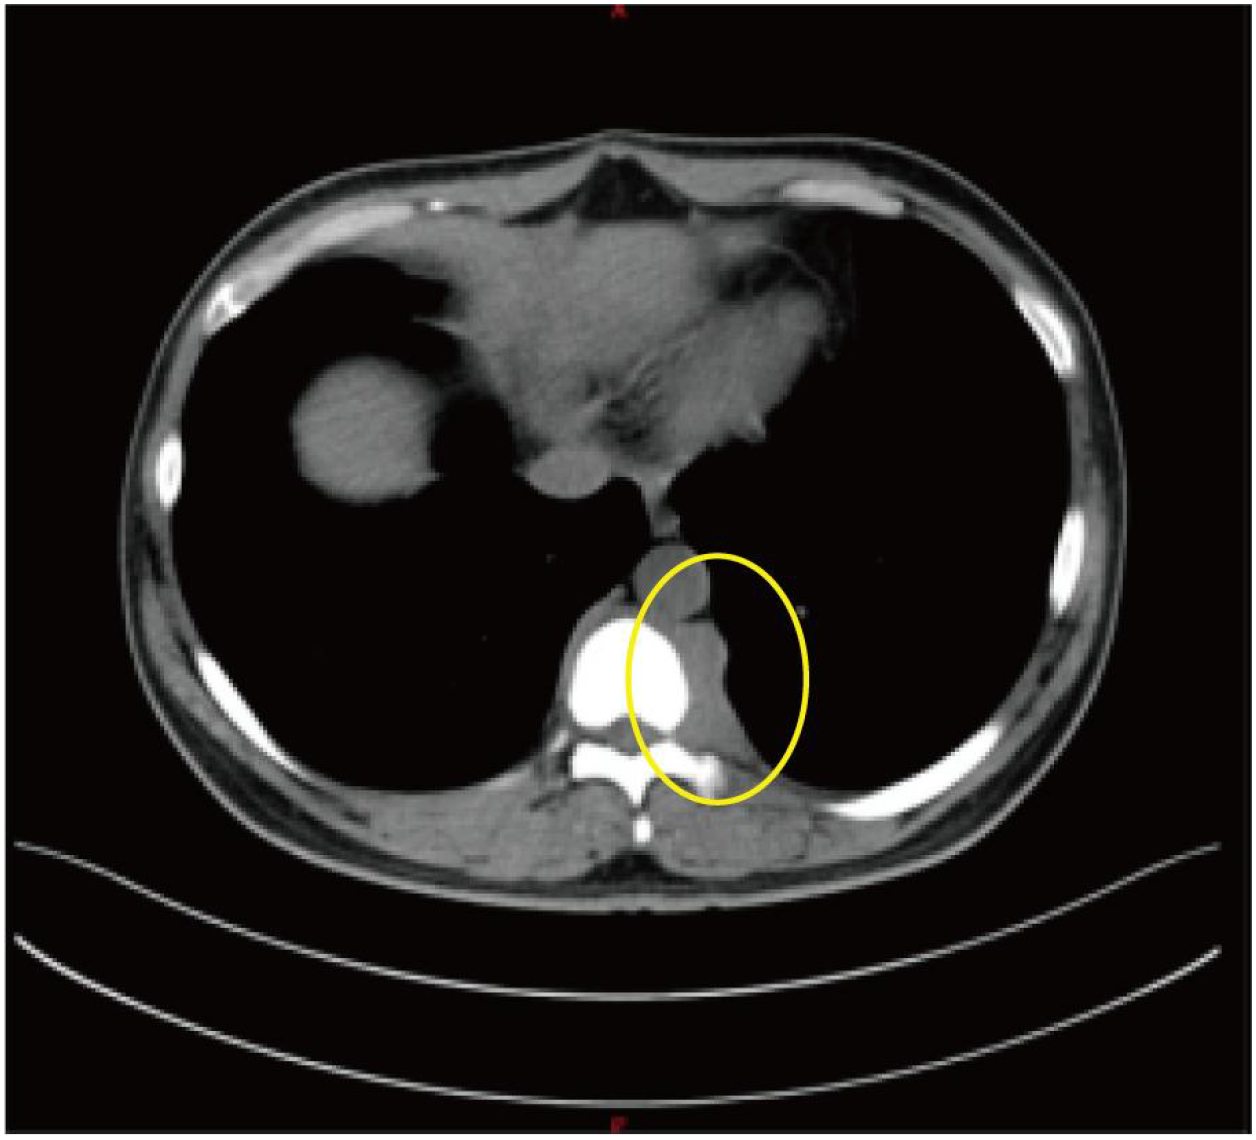

Background Acute promyelocytic leukemia (APL) caused by the TTMV::RARA fusion gene is extremely rare, with fewer than 10 formally reported cases worldwide, and routine molecular tests often fail to detect it. This case is unique because the disease first manifested as vertebral myeloid sarcoma. Although bone marrow morphology and immunophenotyping strongly suggested APL, routine diagnostic methods could not confirm the disease, and the final diagnosis relied on whole- transcriptome sequencing. Case Summary A 39- year- old man was admitted for persistent lower back pain and limited movement of the left lower limb. Imaging revealed destruction of the T9 vertebral body with paravertebral and mediastinal soft- tissue masses. Pathology of the resected mass confirmed myeloid sarcoma. The patient developed pancytopenia and coagulopathy. Bone marrow morphology and flow cytometry showed classic features of APL, and all- trans retinoic acid (ATRA) induction therapy was initiated. However, PML:: RARA PCR and RARa FISH were negative, fusion gene screening and karyotyping found no abnormalities, and the diagnosis was revised to AML, prompting a switch to IA chemotherapy. As the diagnosis remained unclear, whole- transcriptome sequencing was performed and revealed a TTMV::RARA fusion, which was confirmed by RT- PCR. The patient was ultimately diagnosed with TTMV::RARA APL. He later discontinued treatment and died months afterward. Conclusion This report presents a rare adult case of TTMV::RARA acute promyelocytic leukemia presenting as vertebral myeloid sarcoma. Whole-transcriptome sequencing was essential for diagnosis after routine molecular tests were negative, highlighting the importance of considering rare RARA fusions in APL-like cases lacking PML::RARA. TTMV::RARA APL may be sensitive to ATRA/ATO-based therapy; however, the patient discontinued treatment. Further cases and clinical experience are needed to optimize management strategies for this rare APL subtype.